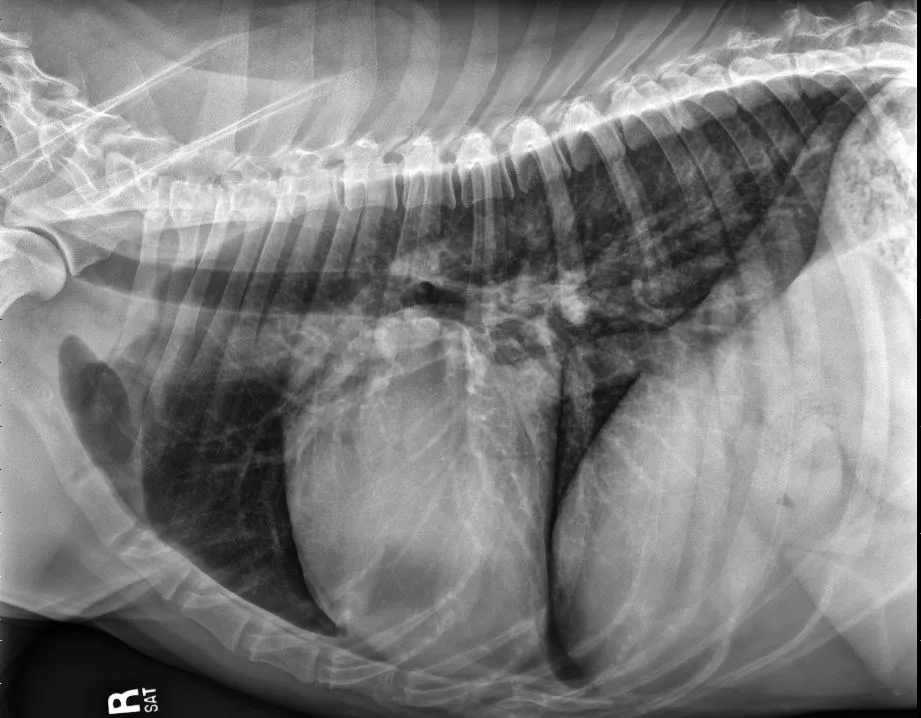

A subset of patients with acquired heart disease may develop left-sided congestive heart failure (CHF). In addition to left-sided cardiomegaly, dogs with active CHF secondary to MMVD commonly exhibit lobar pulmonary venous enlargement on radiographs, as well as an interstitial to alveolar radiographic lung pattern that typically develops in the perihilar region and right caudal lung lobes (Figure 8); however, in dogs with DCM, this lung pattern may be seen in the ventral lung lobes (Figure 9). The radiology lung score is an objective method to quantify severity but was not associated with the recurrence of CHF or survival in one study.16 Dogs administered diuretics may not have pulmonary venous dilation, and some dogs with CHF secondary to acute increase in left atrial pressure (eg, aortic valve endocarditis, chordae tendineae rupture) may not have significant cardiomegaly.

FIGURE 9 DV (left) and right lateral (right) projections consistent with left-sided CHF in a dog with advanced DCM. Perihilar to ventral distribution of the severe interstitial to alveolar pulmonary pattern is present in addition to cardiomegaly. VHS, VLAS, M-VLAS, and VRHi collected from the right lateral view are 11.5, 2.1, 4.1, and 3.1, respectively. (Note: The DV image is flipped to display the right side of the patient to the left.)